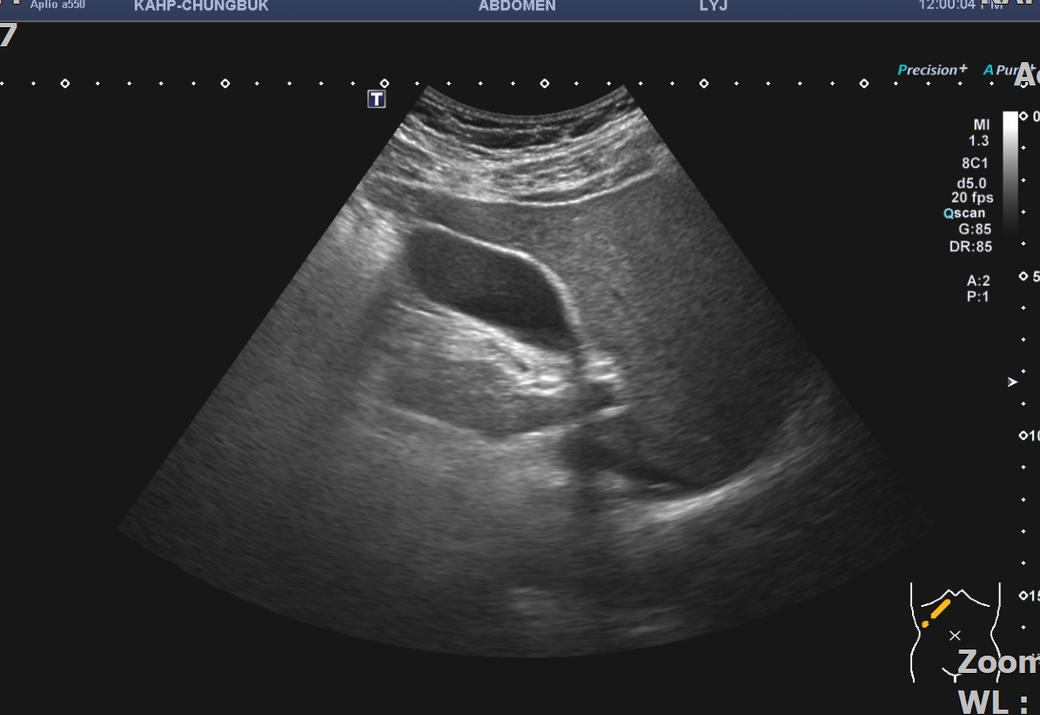

복부초음파 신장 물혹 보이나요? 사진올려봐요

신장물혹 0.6cm mri에는 나오는데 복부초음파에는 소견이없어서요

• 3번 째 사진

올려주신 사진 중 우측 신장이 찍힌 영상은 한 장이며 단면 영상만으로는 물혹 유무를 확인할 수 없습니다.